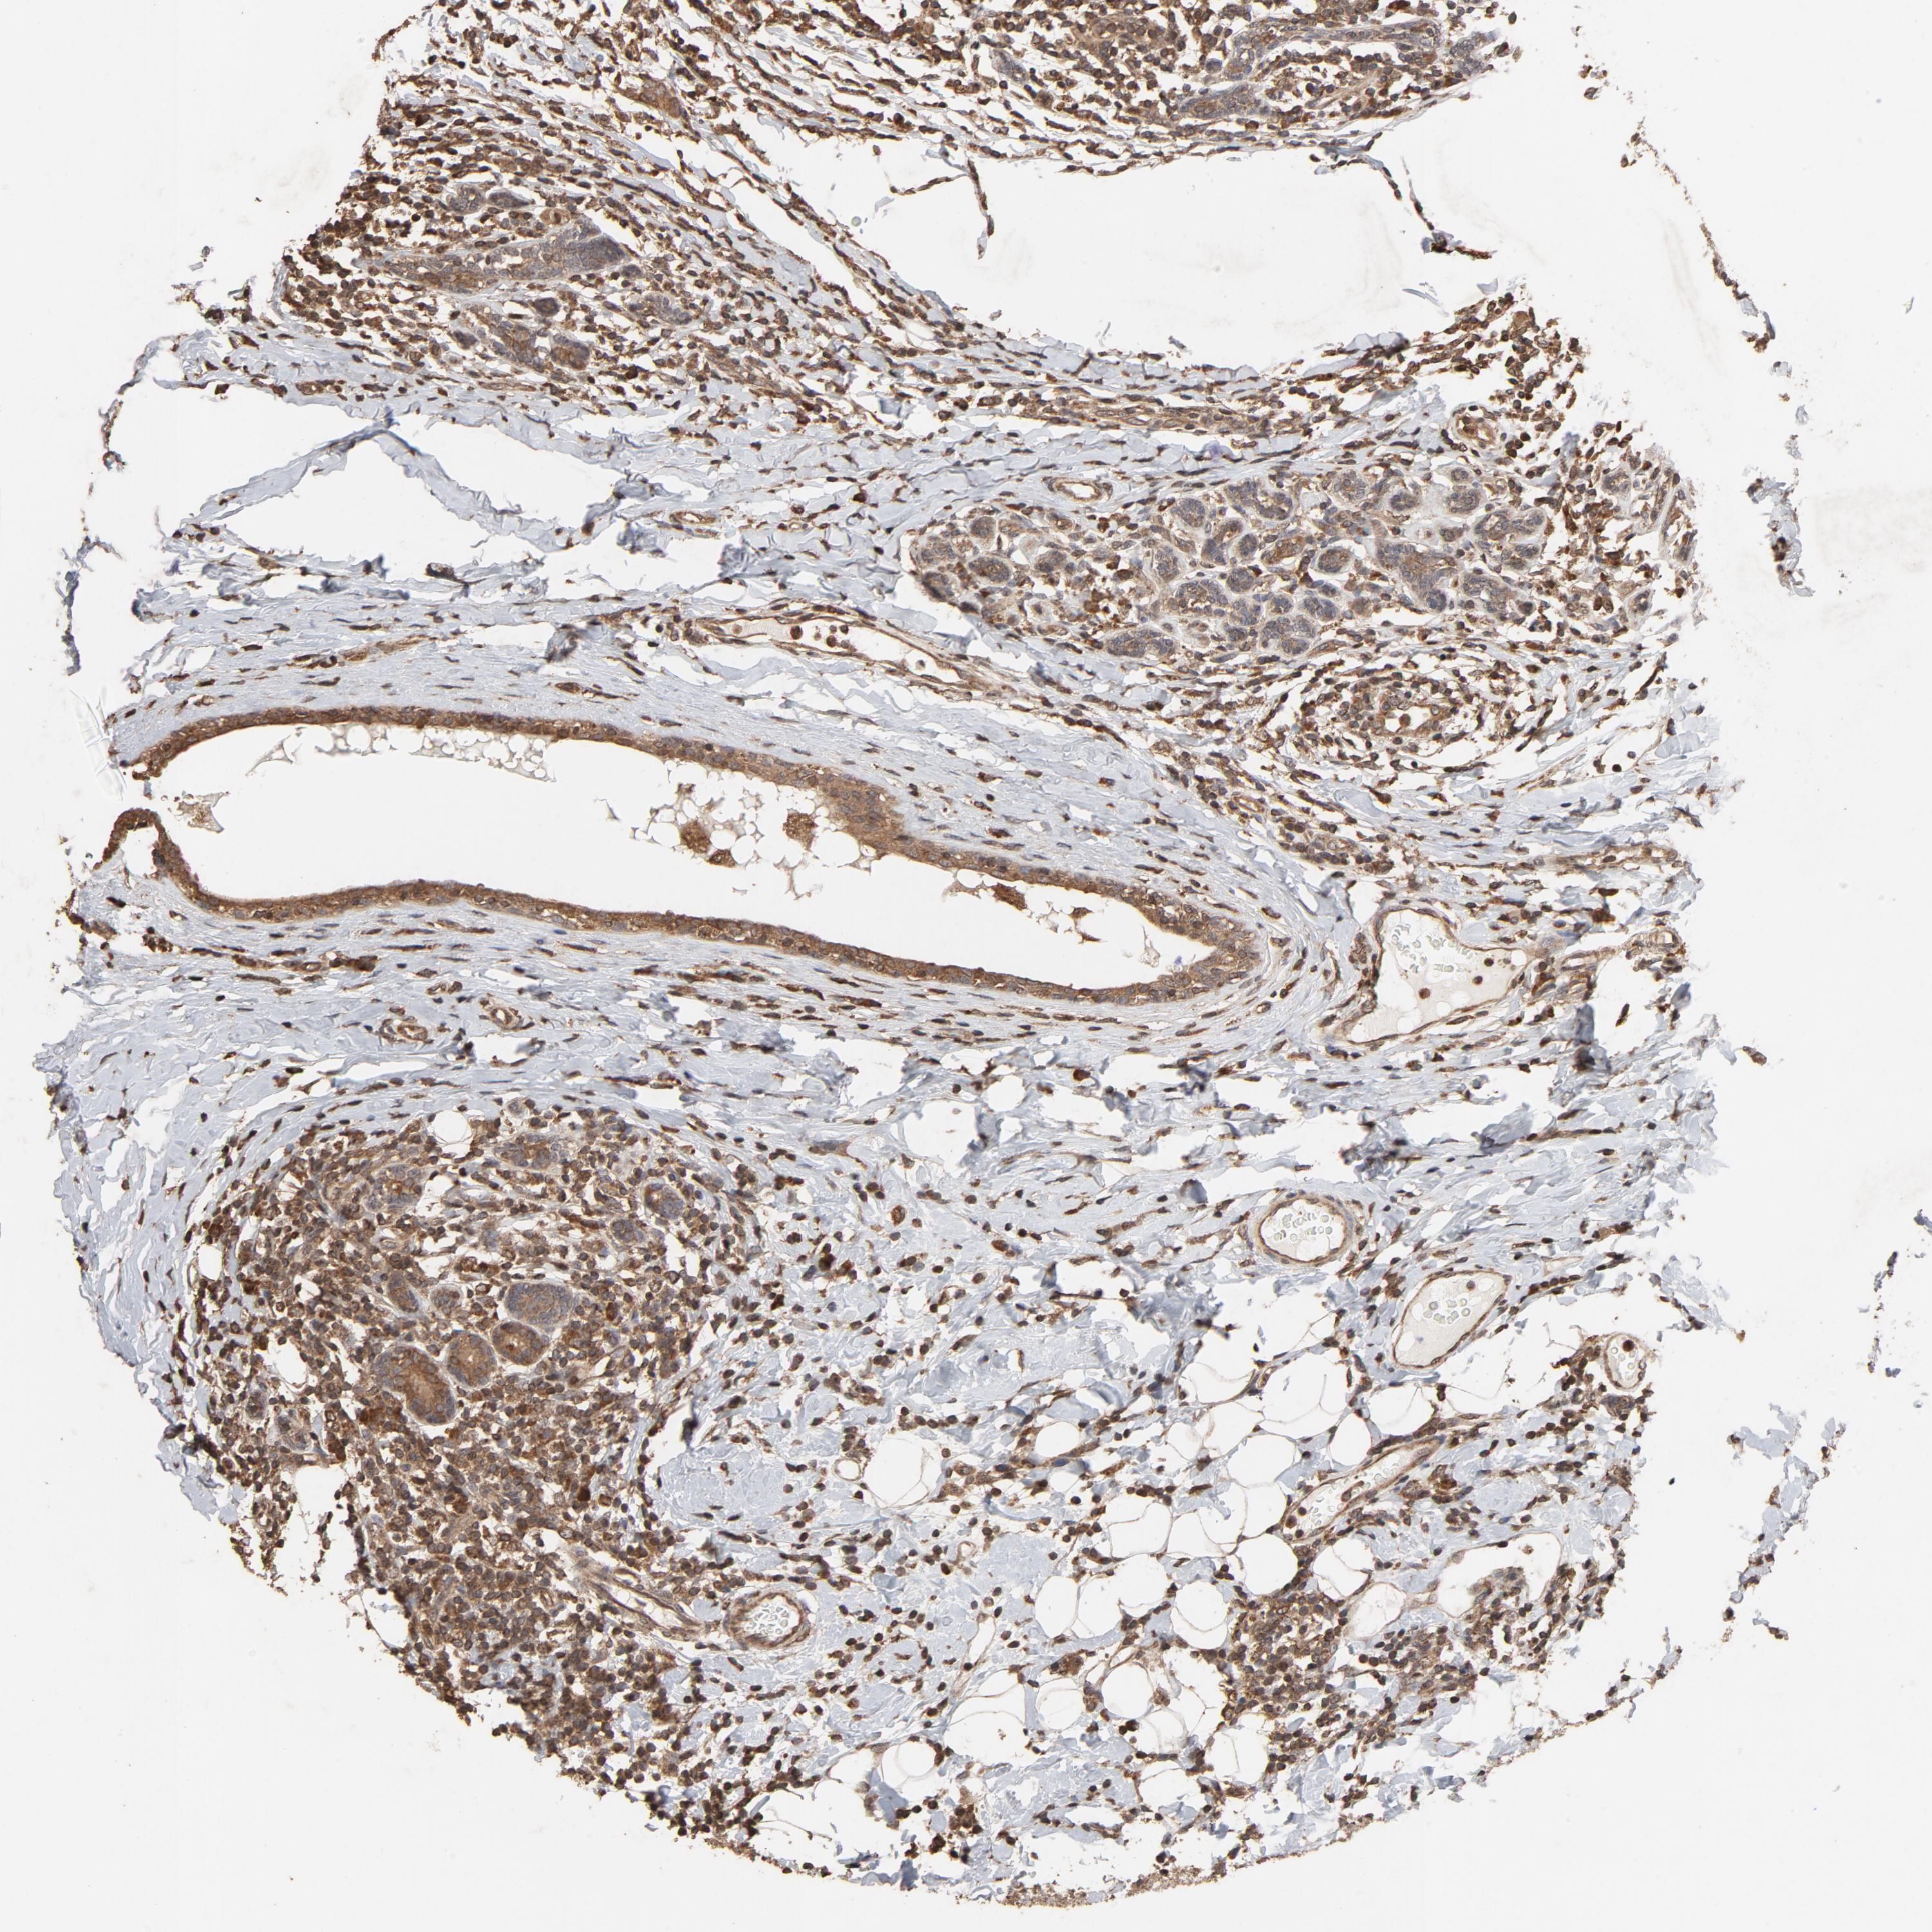

CDC42

CANCER BREAST CANCER Show tissue menu

BRCA TCGA BRCA VALIDATION PROTEIN EXPRESSION